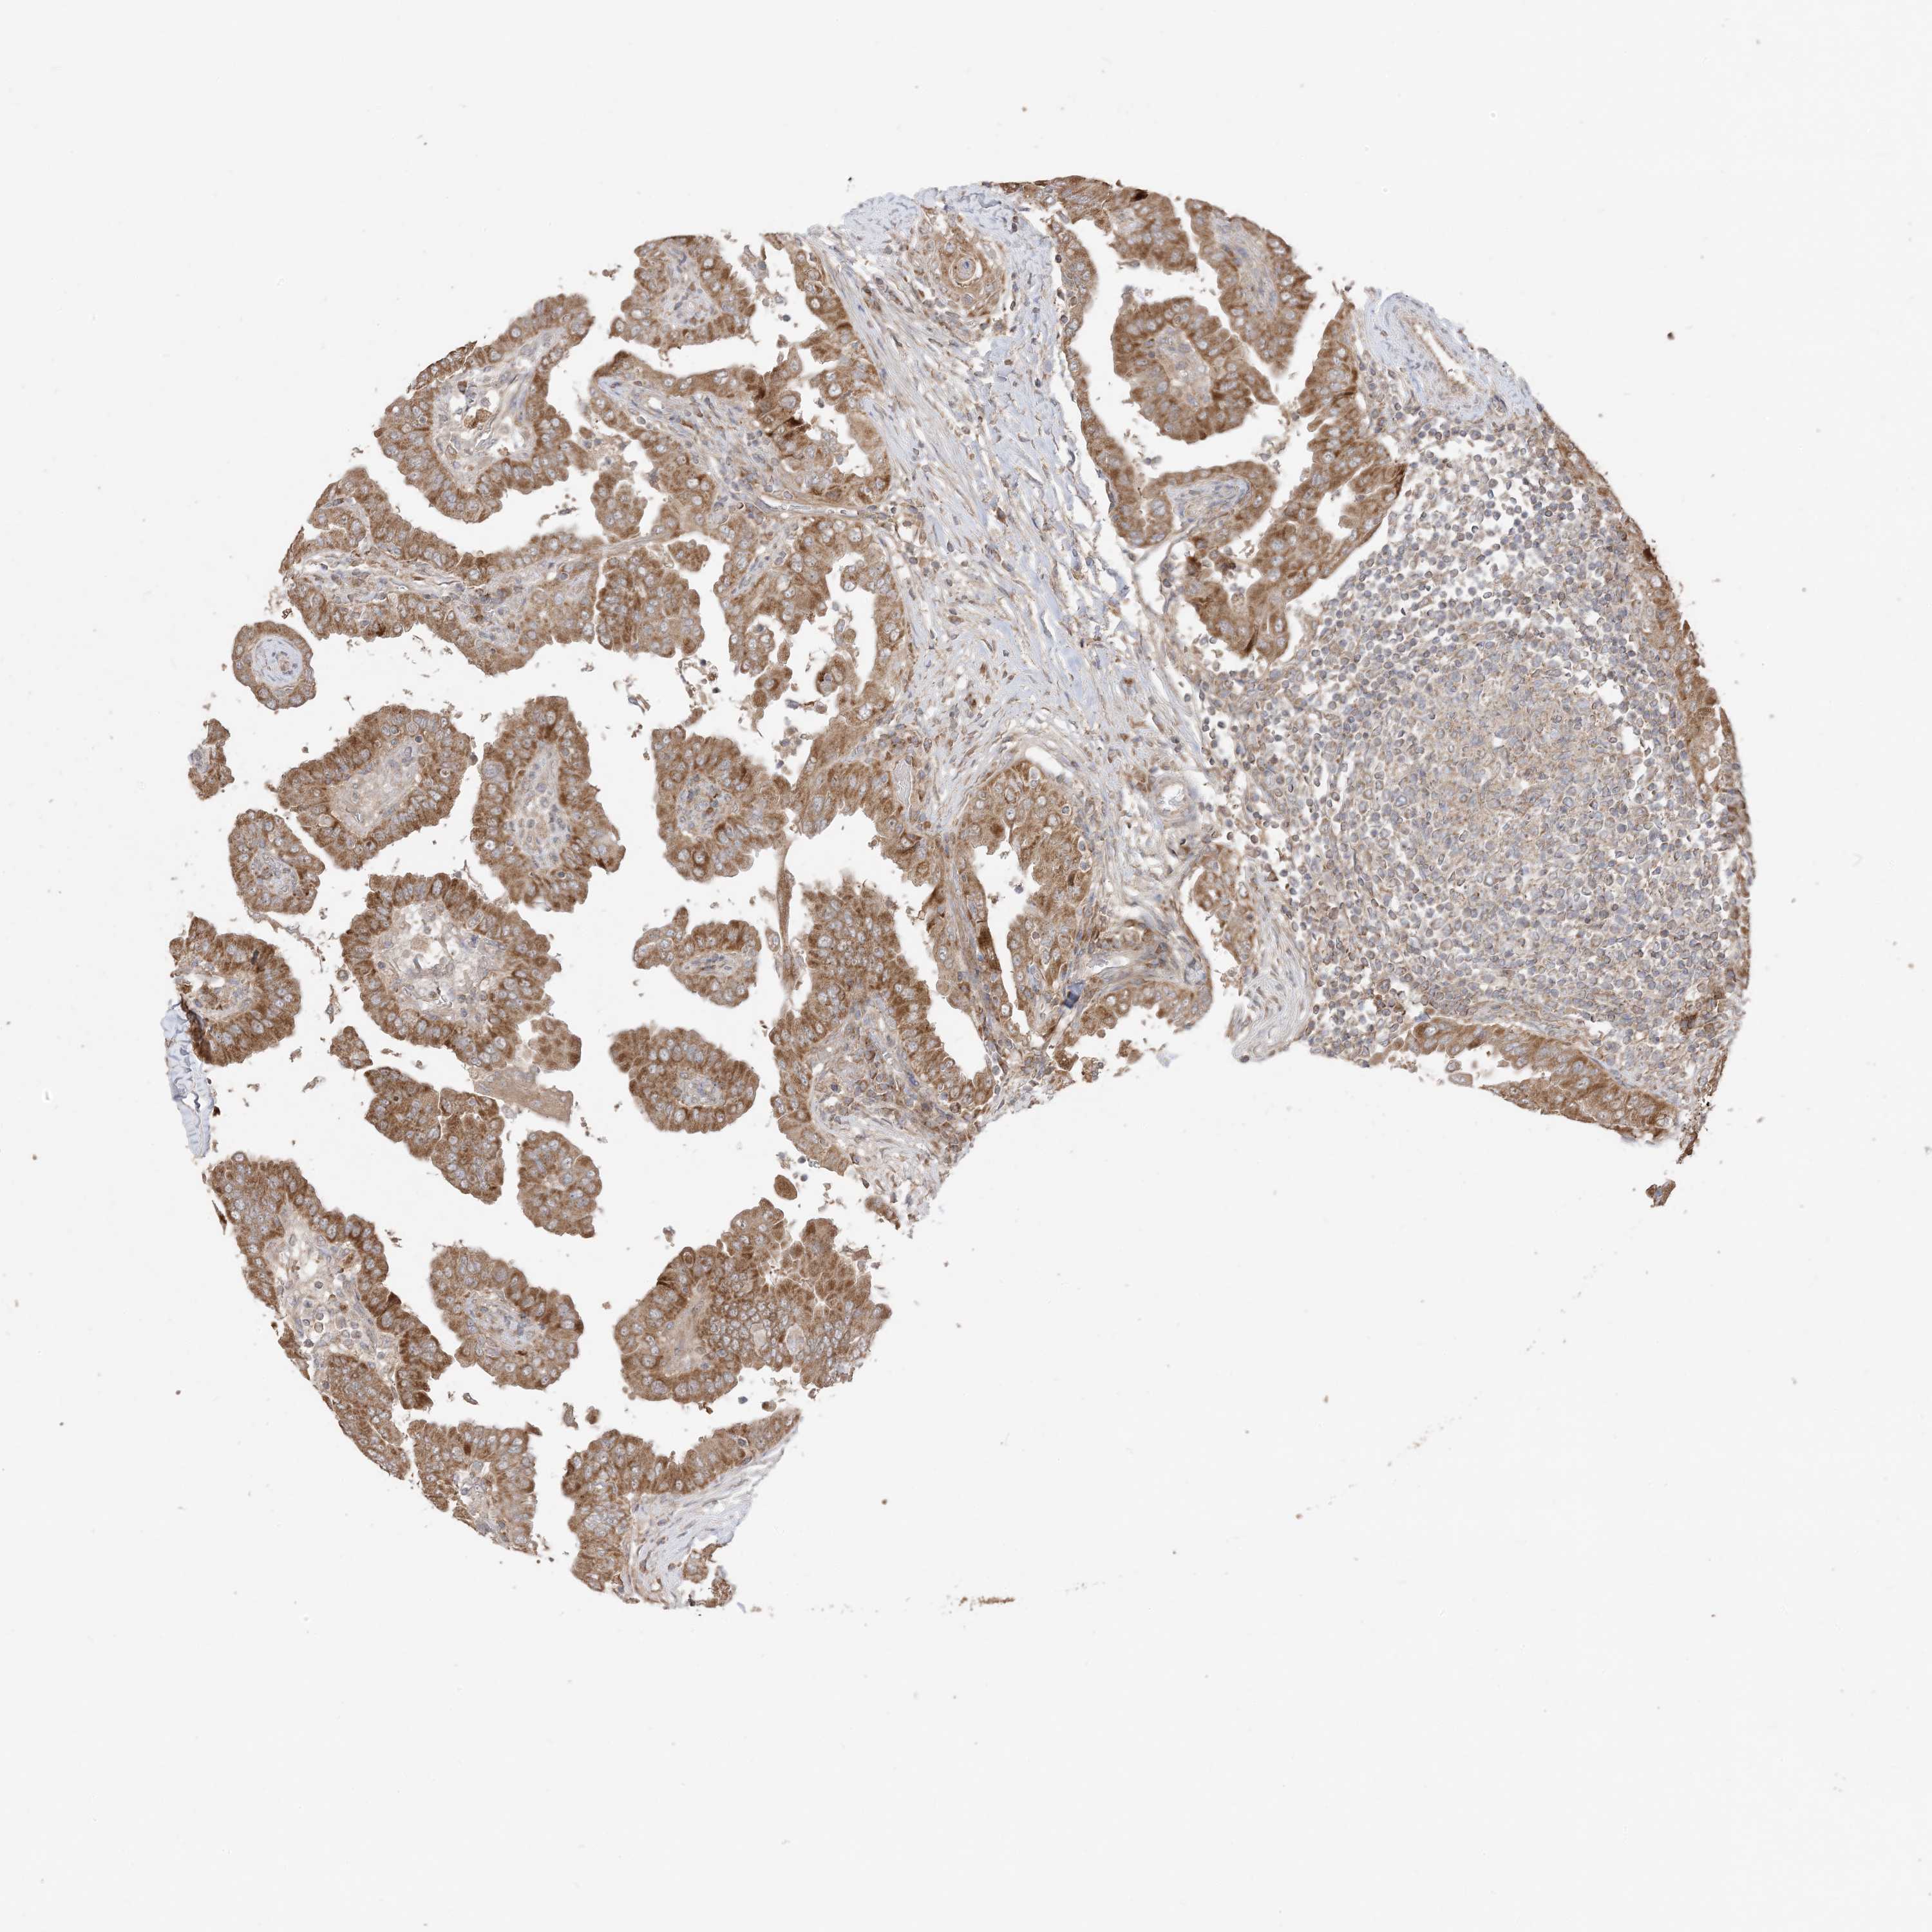

THYROID CANCER - Protein expressioni

A mouse-over function shows sample information and annotation data. Click on an image to view it in a full screen mode. Samples can be filtered based on level of antibody staining by selecting one or several of the following categories: high, medium, low and not detected. The assay and annotation is described here.

Note that samples used for immunohistochemistry by the Human Protein Atlas do not correspond to samples in the TCGA dataset.

Antibody stainingi

Antibody staining in the annotated cell types in the current human tissue is reported as not detected, low, medium, or high, based on conventional immunohistochemistry profiling in selected tissues. This score is based on the combination of the staining intensity and fraction of stained cells.

Each image is clickable and will lead to virtual microscopy that enables deeper exploration of all samples and also displays staining intensity scores, fraction scores and subcellular localization as well as patient and tissue information for each sample.

Antibody CAB037142

Staining

High

Medium

Low

Not detected

Intensity

Strong

Moderate

Weak

Negative

Quantity

>75%

75%-25%

<25%

None

Location

Nuclear

Cytoplasmic/membranous

Cytoplasmic/membranous,nuclear

Papillary adenocarcinoma, NOS

Follicular adenoma carcinoma, NOS